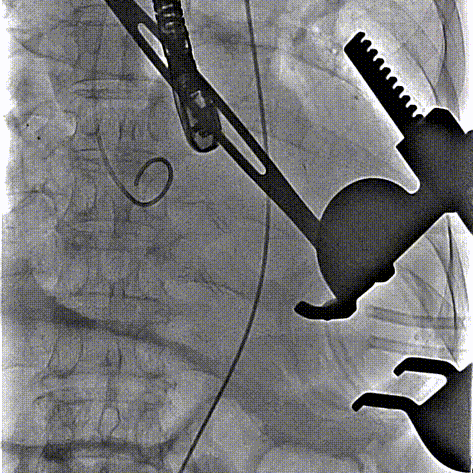

术中回顾及效果

在DSA与超声引导下,手术团队高效精准地完成了瓣膜的定位、释放与功能评估。手术过程顺利,夹持件入窦与定位一气呵成,三枚夹持件的释放与锚定位置与术前评估完全一致,器械用时仅6min左右。患者主动脉瓣重度反流纠正,术后无反流、无瓣周漏。术后心脏彩超显示人工生物瓣启闭良好,平均跨瓣压差3mmHg,流速正常,舒张压从30mmHg提升至70mmHg。

夹持件顺利入窦

夹持件入窦后撤内鞘

瓣膜释放

术后造影